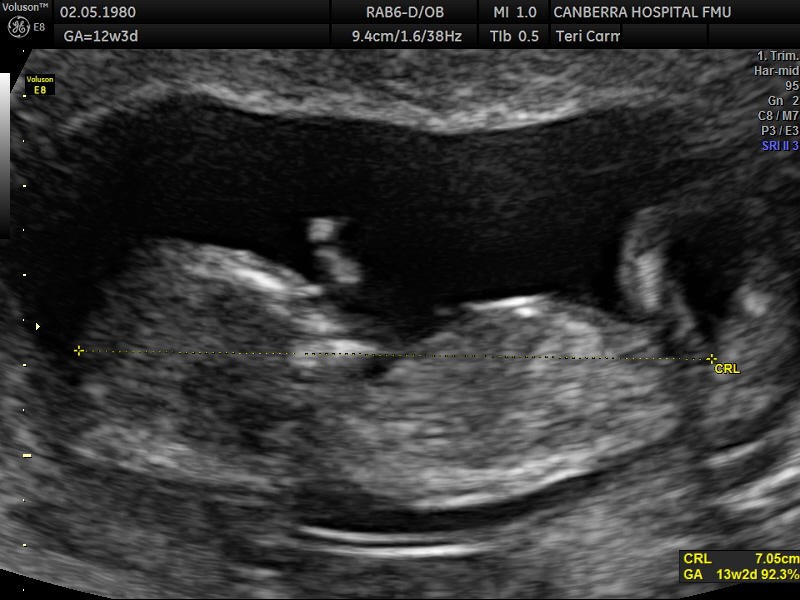

Its been ages once I've been on here but I'm back and pregnant!! I posted my pics on a FB nub theory page but didn't like their guesses :p (Lol!) so would love your thoughts. The scan was done at 12 weeks and 3 days but bub was measuring 13weeks exactly. Attachment 35124Attachment 35125Attachment 35126

Looks like a boy to me as a guess. [emoji170]

Boy from the last pic

Boy; stacking on last image and looks pretty short in second image x